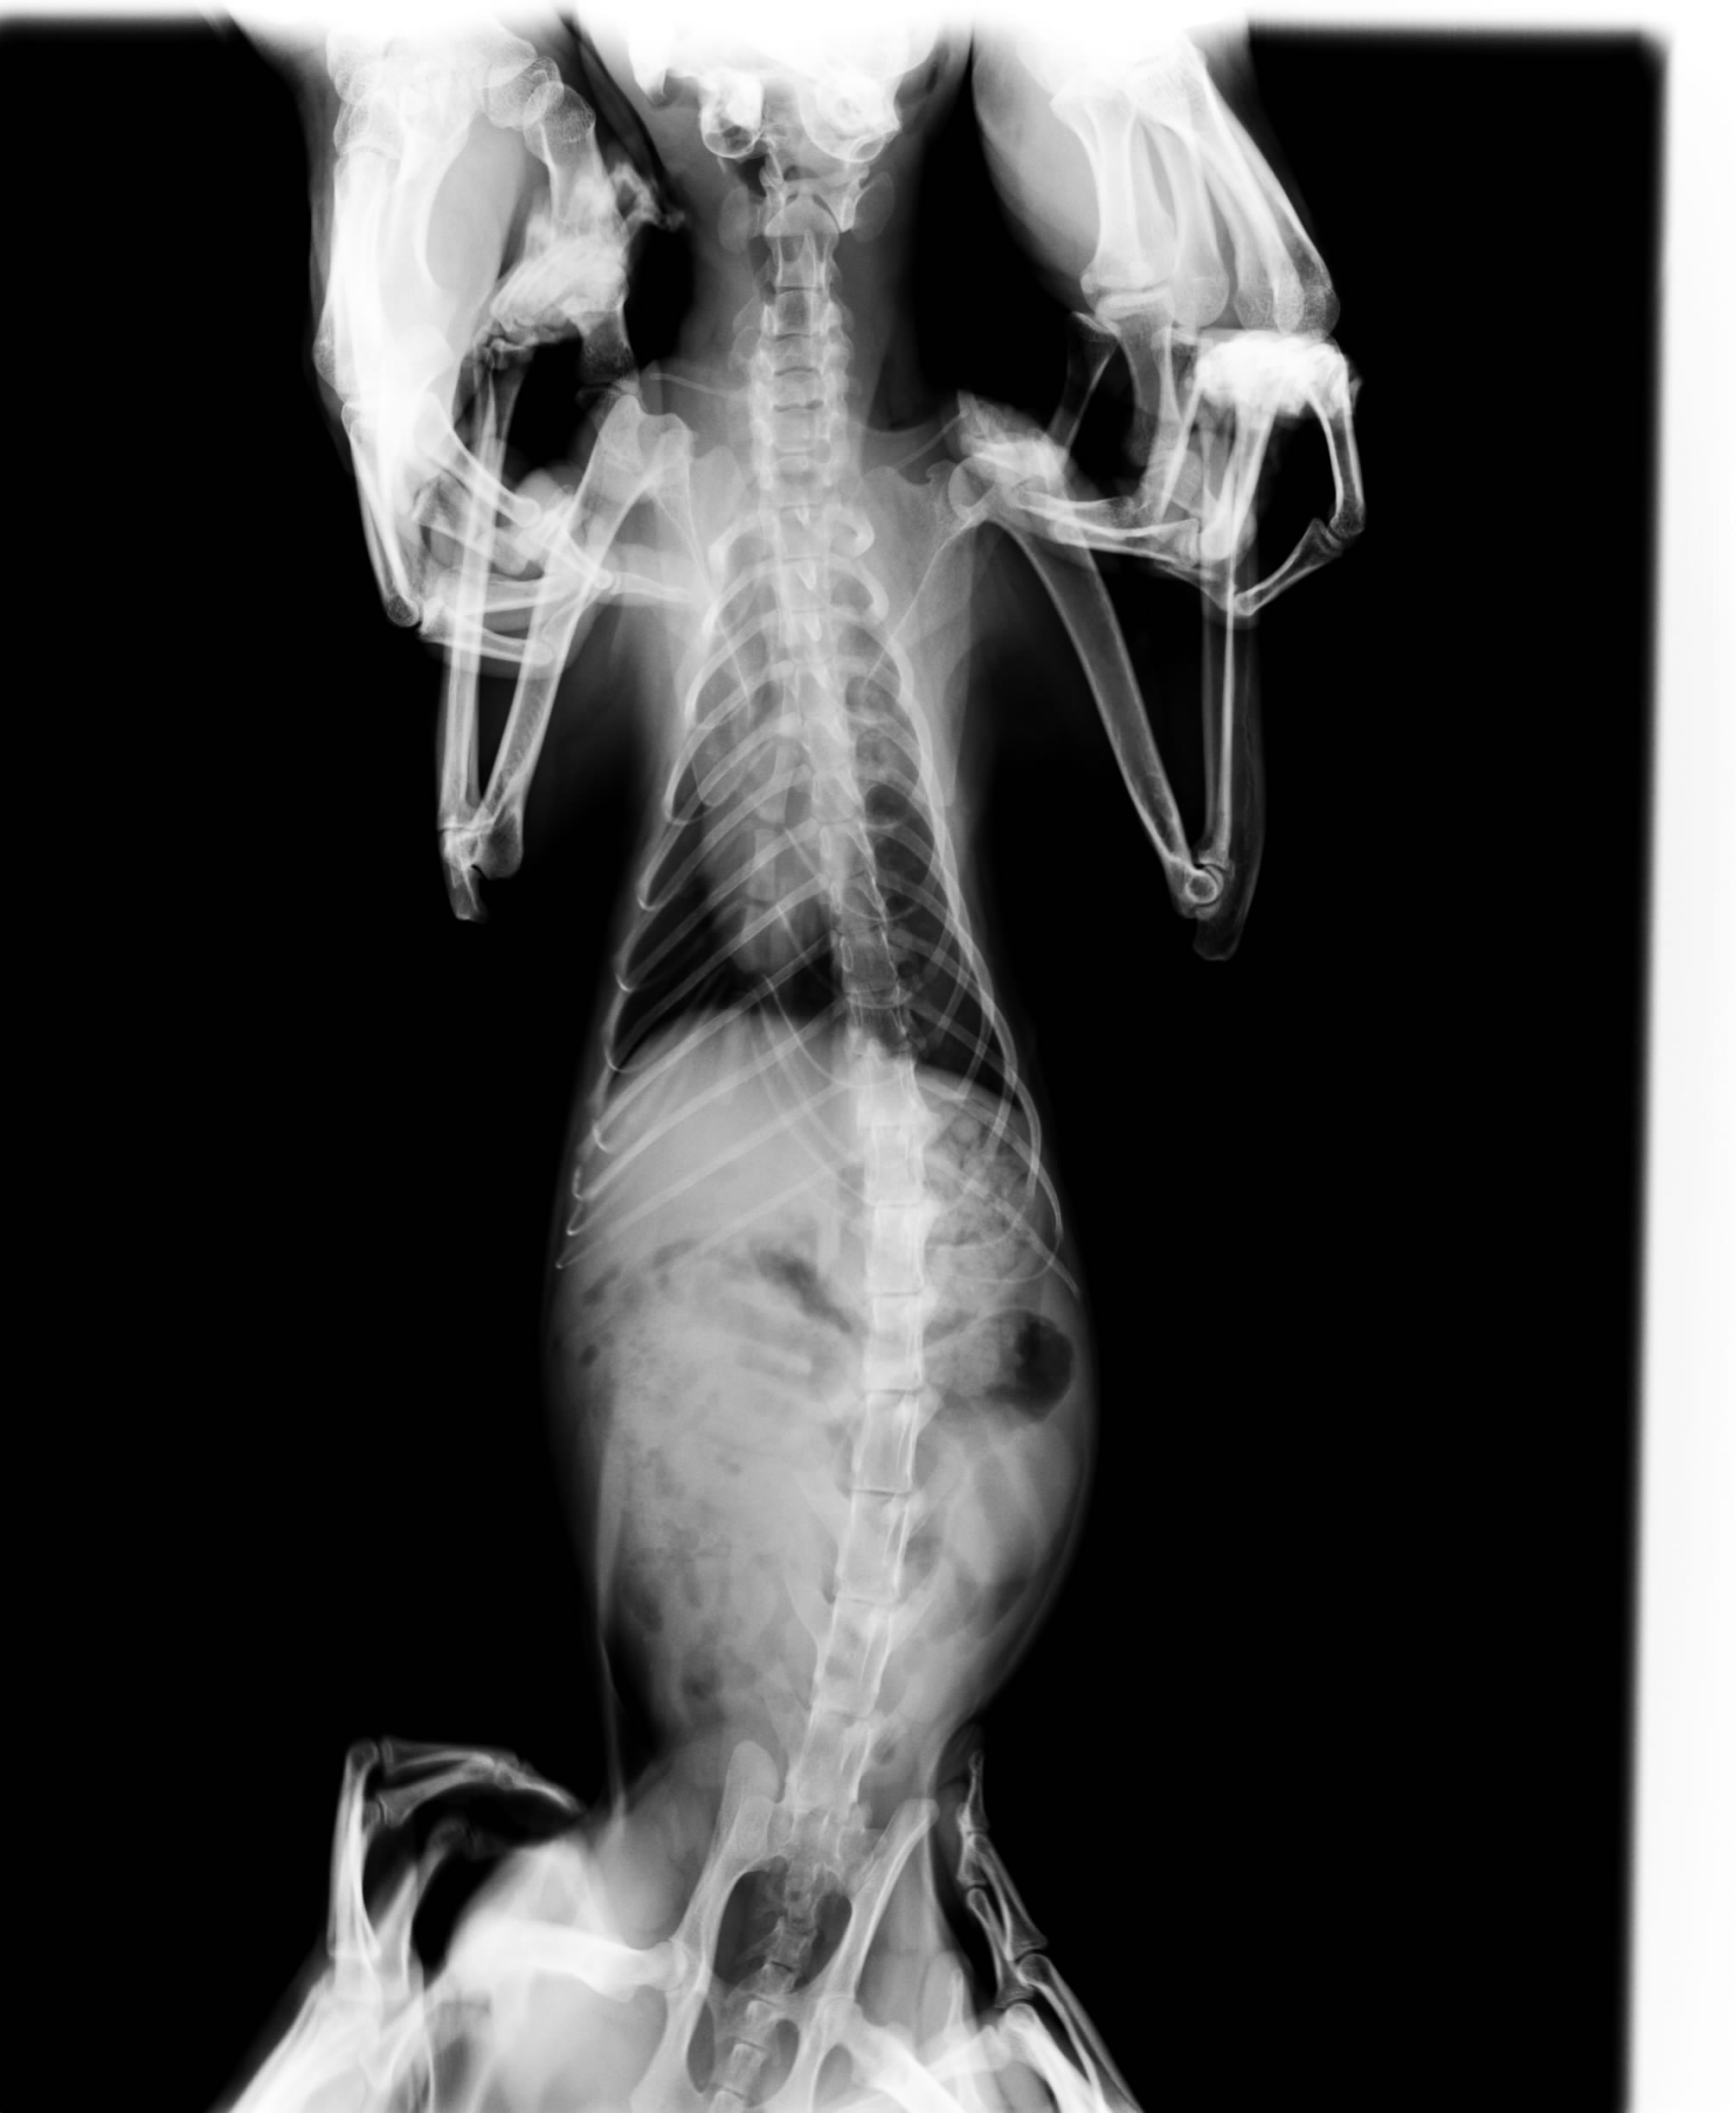

主題: 血尿齒槽膿瘍不肯進食的瘦橘貓 申請者姓名: meowtain 花色: 申請日期: 2015-01-22 23:56:13 申請者部落格: 申請者臉書網址: 所在縣市/合作醫院: 台中市/春天動物醫院 治療費用: 7000元 需求人數: 9人 已結案 (2015-02-24 12:34:24) 報名人員: JASON(已付款)、Rean Wu x2(已付款)、Jessica Chen(已付款)、林西吉(已付款)、Ting Huang(已付款)、Patrick x3(已付款)、 候補人員: 動物病情說明: 呆呆是我餵養了一段時間的浪貓,一開始瘦到只剩皮包骨,很親人撒嬌,總是掛著綠色鼻涕,食慾一直都不太好,只餵胖一點點。

最近他又兩天不吃,連給他最愛的水煮雞肉他還是蹲著不動只看著我,發出帶有濃痰的咳嗽聲,做出尿尿姿勢好久才尿出來,而且還是帶血的泡沫尿,於是趕快把虛弱的他送醫。

檢查發現體溫只有36.5,輕微脫水,白血球偏高,腎指數是一般貓的兩倍多,牙齦化膿,膀胱發炎,需要住院做進一步的治療。

8500的醫藥費扣除我的自付額後,尚須7000元,謝謝各位貓咪天使的幫忙。動物近況說明: 經過三天住院治療,阿呆順利出院了,鼻涕少了很多,嘴巴也不再像以前一樣發出惡臭。食慾變得不錯。